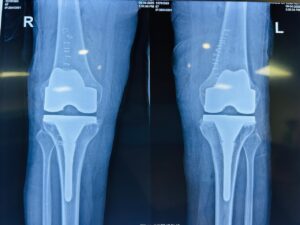

AFTER SURGERY WITH NAVIGATION – COMPLETE CORRECTION